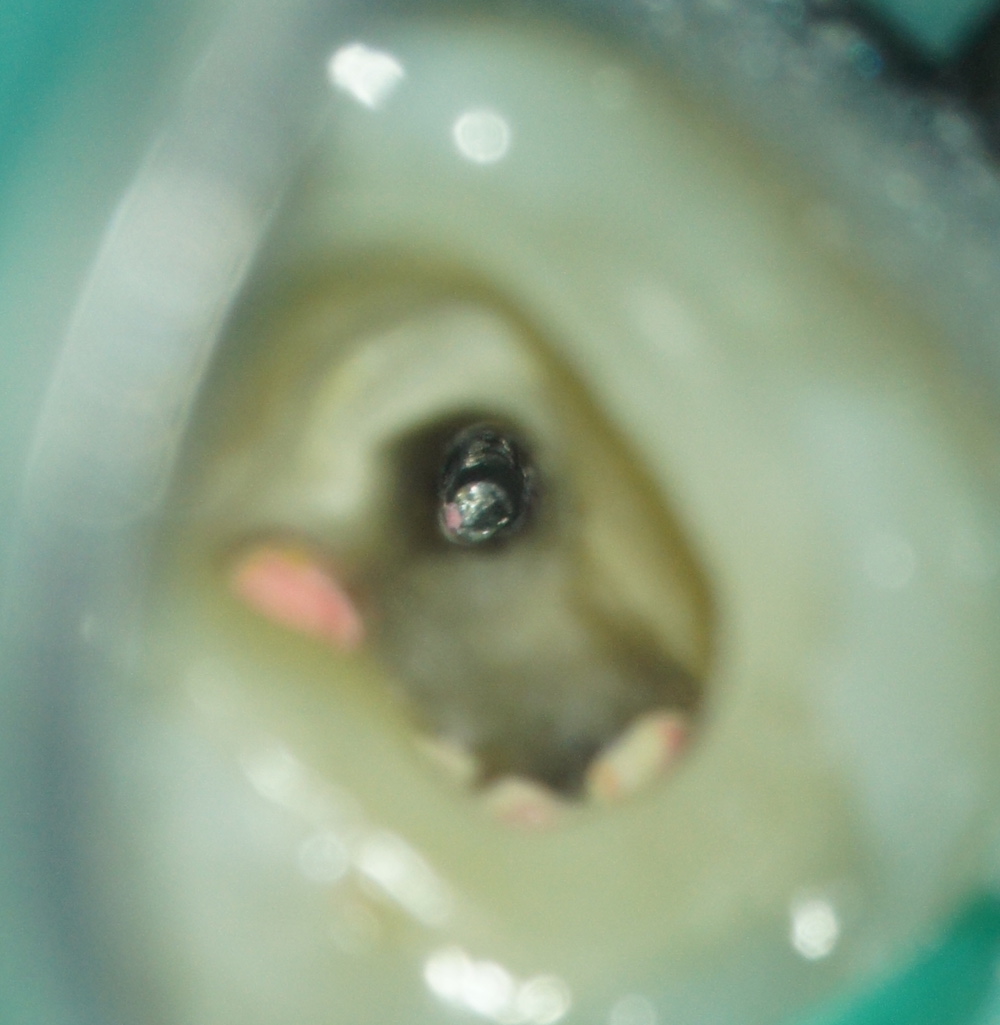

La tête de fragment est découverte à l’aide de limes U (taille 15/20) dégageant un diamètre de 0.5mm seulement. On glisse ensuite une boucle ajustable de fil autour du fragment.

Une fois serrée autour du fragment, celui-ci est extrait en tirant sur le fil.